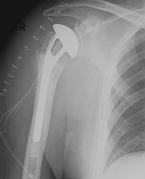

Fracture prostheses for complicated humeral head fractures

left: X-ray of a humeral head fracture before treatment with a fracture prosthesis.right: X-ray of a humeral head fracture after treatment with a fracture prosthesis